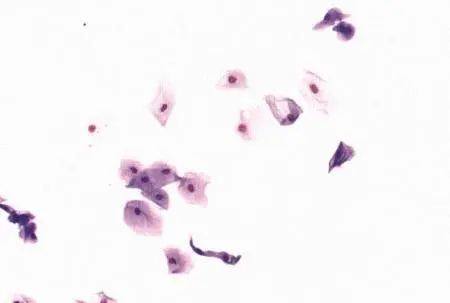

Рассматриваются следующие вопросы: нормальная физиология собак и кошек; болезни репродуктивной системы; бесплодие самок и бесплодие самцов; нормальное функционирование и дисфункция молочных желез; спаривание; искусственное осеменение; протекание беременности и роды; уход за новорожденными щенками и котятами, их наследственные и инфекционные болезни; техника оперативных вмешательств на репродуктивных органах; фармакологический контроль репродукции.